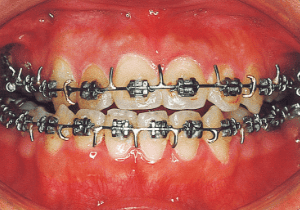

On the lateral cephalometric radiograph, the vertical height of the face appears greater than its depth. The lower facial height is also high, suggesting a shape somewhat prone to developing a protruding lower bite, though this does not raise significant concern (6). The facial photograph of front view shows slight asymmetry in the face, but it is not particularly extreme (1). The first phase of treatment corrected the anterior cross bite and deviation, but subsequent growth exacerbated the mandibular deviation, necessitating surgical treatment.

16 Before surgery 7-21-’98 17 years

17 After surgery 8-11-’98 17 years 1 month

Although early treatment improved the slight deviation observed during the deciduous dentition stage, it became apparent that the deviation increased with age, eventually exceeding the limits of treatment. This appears to be an innate deviation, and the developmental pattern observed in this case seems to disregard the occlusion. Four first premolars were extracted (15), crowding was corrected and space closure was performed (16), and surgical intervention improved the deviation (17).